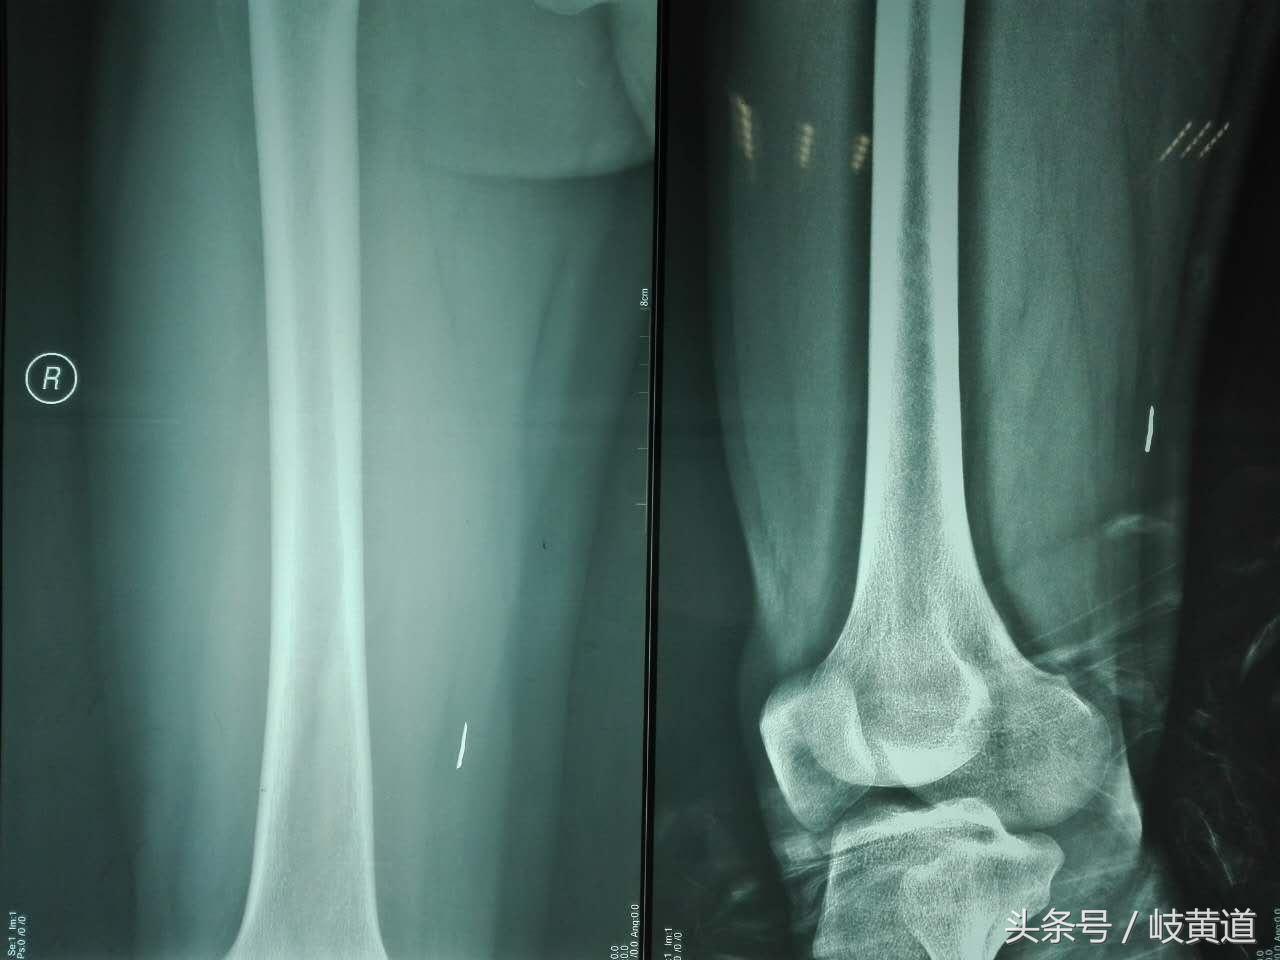

这位患者是下午被工友背进急诊室的,说是大腿扎了个钢渣,当时右大腿内侧靠近膝关节的地方有一个约2mm的小洞,有少量渗血,查体局部摸不到异物,股静脉和大隐静脉没有损伤,于是让他去拍个局部的X线片。

拍了X线片后可以清楚的看到右大腿内侧肌层有一个约2厘米长的棒形异物,于是我们决定:对室内进行常规消毒后直接在透视床上就地展开手术“切开探查取异物”。因为:第一,患者的异物距体表至少有4厘米,比较深且距股动脉很近,稍有不慎异物就有可能划伤股动脉。股动脉一旦破裂其喷射压力相当于高压水枪,后果严重;第二,肌肉已将异物包绕推移,在搬动活动下肢异物的位置还会移动,不好掌控;第三,在透视机上做手术,可以随时拍片定位。经过2次定位和2小时的紧张手术成功取出异物,手术过程虽然有困难,但总算在没有造成严重后果的情况下取出异物。